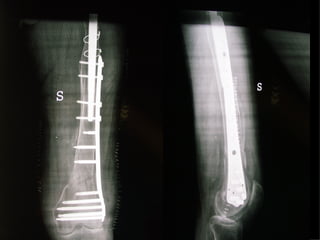

INDICAZIONI COMUNI Fratture sovracondiloidee Fratture intercondiliodee Fratture diafisarie distali PARTICOLARI Fratture con grave osteoporosi Fratture periprotesiche

VANTAGGI CHIRURGIA MININVASIVA Mini Open Inserimento della placca sottocutaneo per scivolamento Viti percutanee Preservazione dei tessuti molli Ridotto danno vascolare Rapida ripresa funzionale

LISS  NCB

NCB

Conclusioni Riduzione  anatomica Minimo trauma chirurgico Corretto equilibrio fra elasticità e stabilità Precoce mobilizzazione